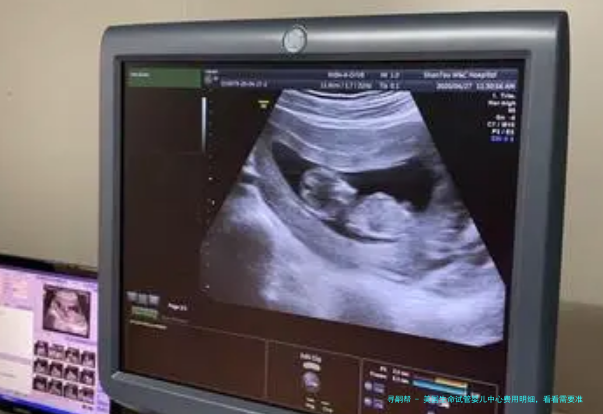

⑴医疗设备:美国生命试管婴儿中心配备了世界上最前沿的医疗设备,囊括超声波监测、卵巢穿刺手术等。

| 超声波监测 | $1,000 |